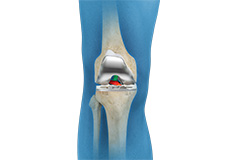

Knee Implants

Knee implants are artificial devices that form the essential parts of the knee during a knee replacement surgery. The knee implants vary by size, shape, and material. Implants are made of biocompatible materials that are accepted by the body without producing any rejection response. Implants can be made of metal alloys, ceramic or plastic, and can be joined to the bone.